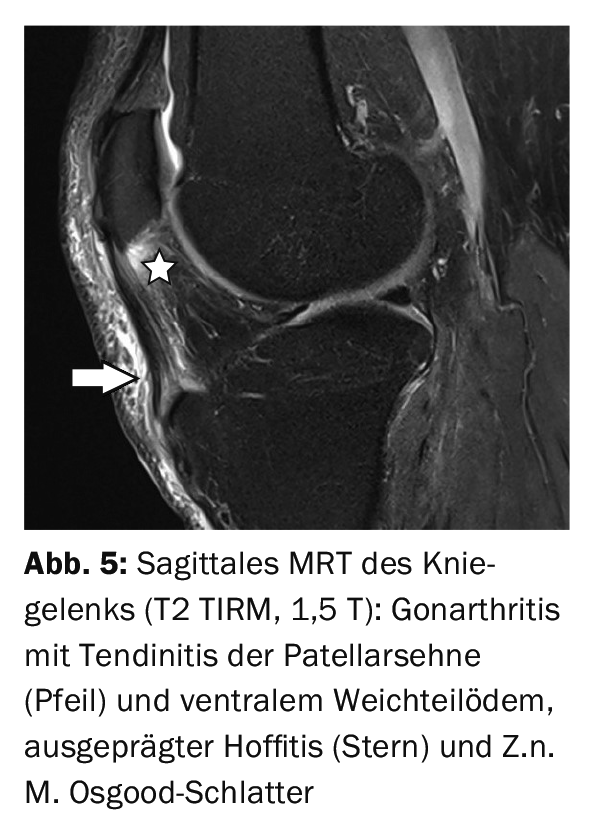

The purpose of MRI is to verify the full extent of the local inflammatory reaction: Soft tissue edema, tendinosis or tendinitis, bursitis, hoffitis, and also spongiosa edema of the tuberosity. Fat-suppressing sequences [6,8] are excellent for this purpose, and contrast medium support is not obligatory. The use of T1w or T2w sequences allows differentiation of concomitant chronic or acute alterations of the patellar tendon.

Case report 4 shows the situation of an activated Osgood-Schlatter disease with spongiosa edema and fragmentation (Fig. 4) after impact trauma in a 53-year-old patient as well as significant soft tissue edema. Case study 5 offers a Z.n. M. Osgood-Schlatter with deformed tuberosity without inflammatory bone reaction rather incidentally in an arthritis of the knee joint with pronounced inflammatory soft tissue reaction (Fig. 5). At Case report 6 documents the course of patellar tendon conversion after patellar dislocation in femoropatellar dysplasia (Fig. 6A and 6B).